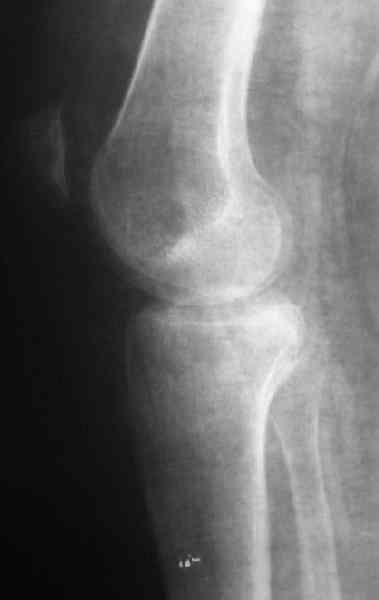

Уважаемый Абдурашид. Если нет противопоказаний , то из оперативных способов, я бы рекомендовал следующие: Полное замещение наружного мыщелка аллотрансплантатом либо открытая репозиция с элевацией и замещение дефекта ауто или аллокостью. В Ваших условиях , я бы рекомендовал второй способ. Во-время элевации необходимо разъединить фрагменты со стороны сустава ( надсечь скальпелем по линиям перелома, а затем тонким остеотомом их разъединить. При помощи долота произвести неполную остеотомию ( захватите не менее 1,5 - 2 см губчатой кости и поднять фрагменты, визуально отрепонировать и фиксировать 2-3 спицами. Дефект заместить костным ауто или аллатрансплантатом. Окончательная стабилизация пластиной ( лучше с угловой стабильностью, либо АВФ - позволит спокойно устранить угловую деформацию.

Недавно поступила больная через 1,5- 2 месяца.